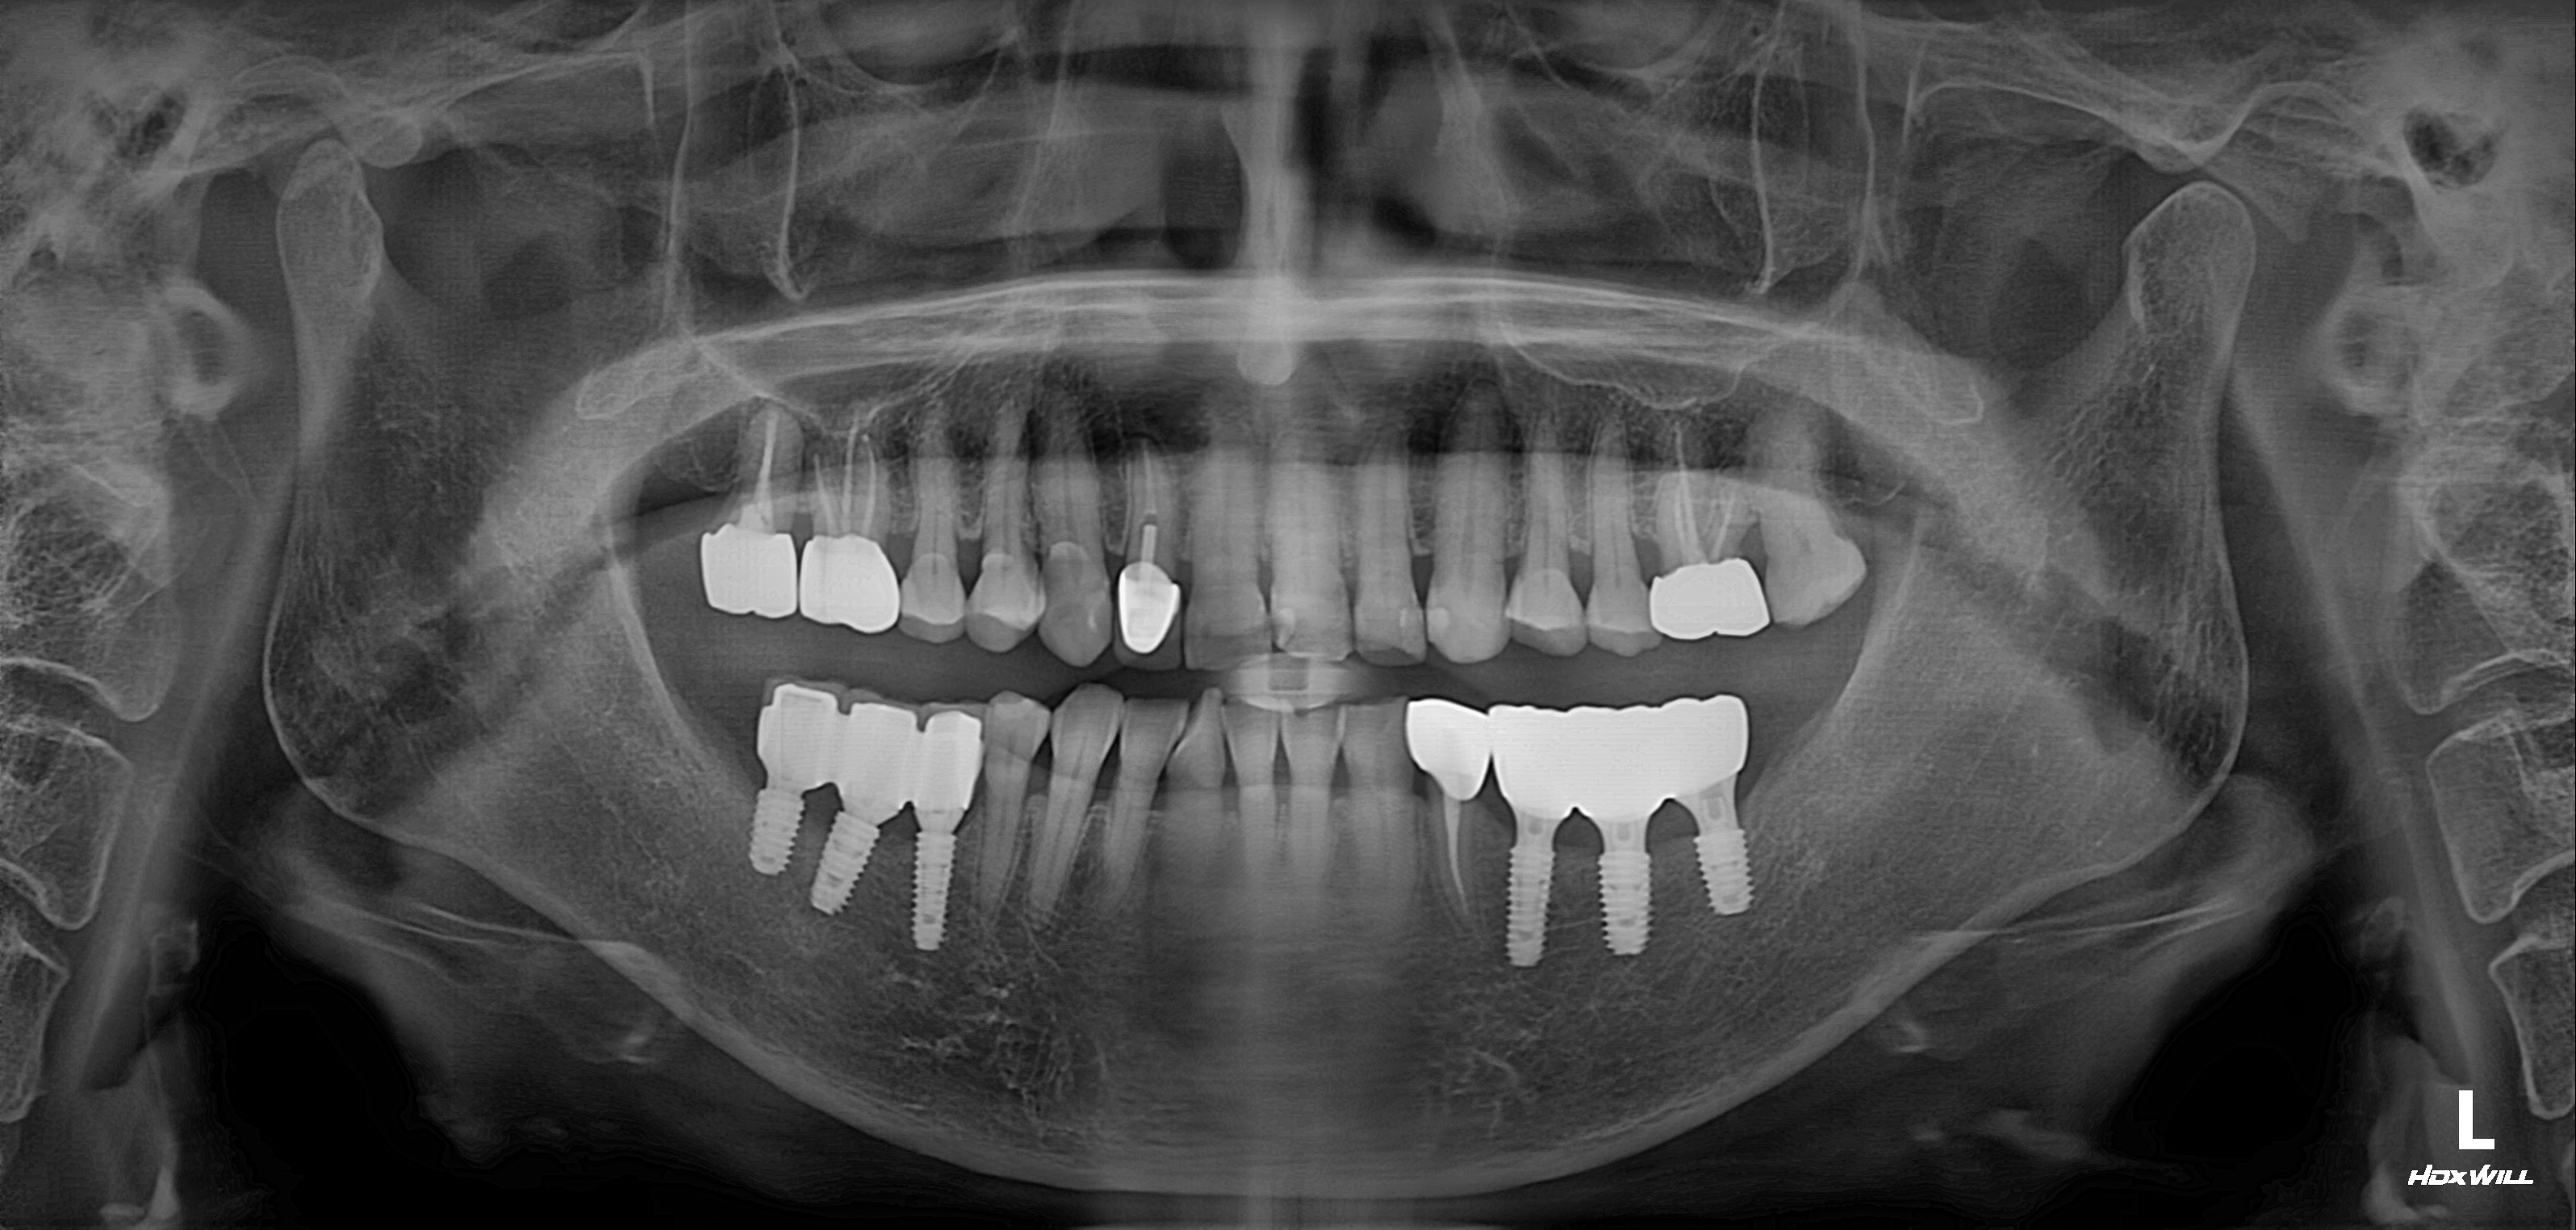

수술 전

수술 후

하악 임플란트 식립사례

전후사진